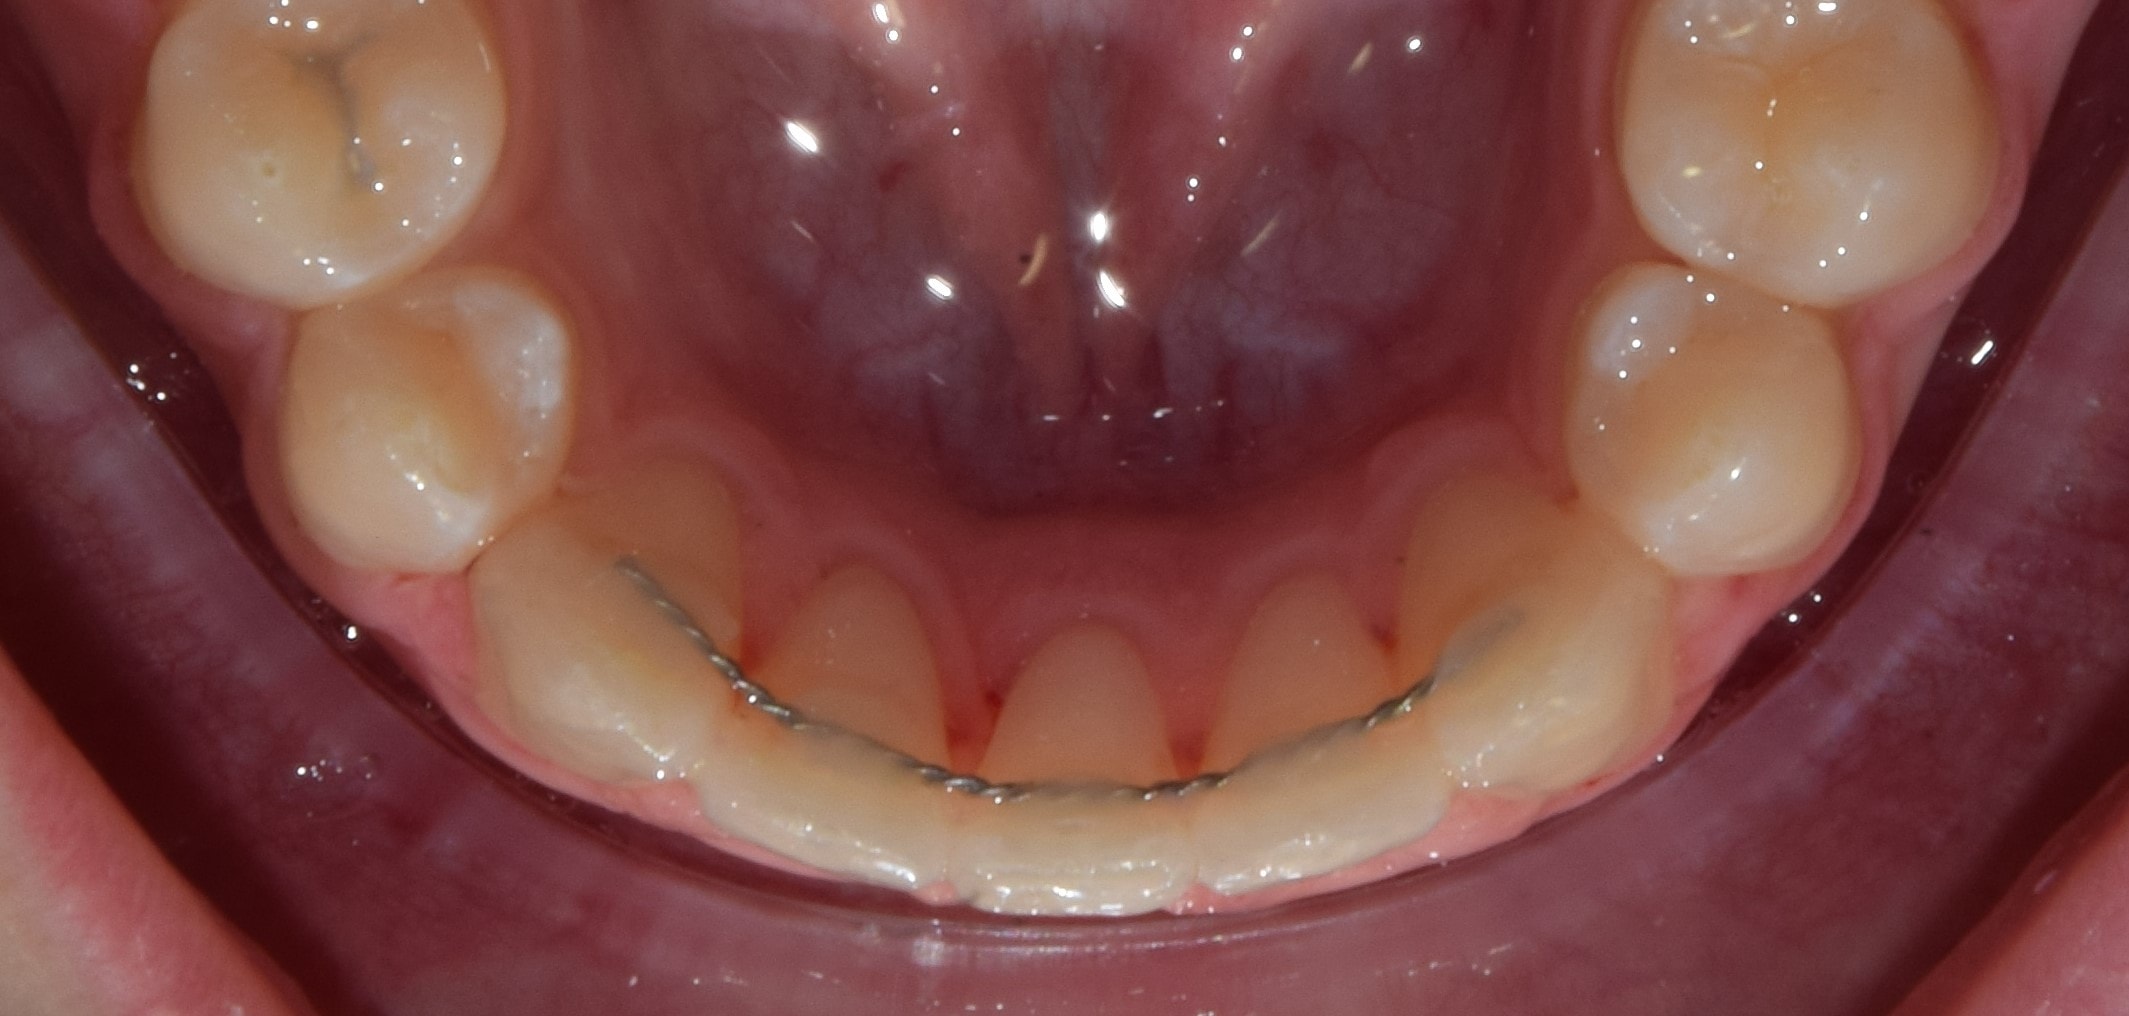

Fix retainer

A fix retainer nem más, mint a fogszabályzó kezelés végén a fogak belső felszínére ragasztott, általában speciális lapos, sodort ív, mely megakadályozza a fogak jövőbeli elmozdulását. Felnőtt fogszabályzás során gyakran használt technika. Felső fogíven kismetszőtől-kismetszőig 4 fogon, az alsó fogíven szemfogtól-szemfogig 6 fogon van rögzítve. Amennyiben lehet, kerülöm a használatát, mert borzasztóan megnehezíti a megfelelő szájhigiénét, illetve előfordulhat, hogy leesnek (általában karácsonykor, vagy munkaszüneti napokon 😊 ). A nem megfelelően beállított fix retainer nem kívánatos fogelmozdulásokat is okozhat! Ez a jelenség nagyon gyakori. A legbiztosabb módszer azonban az elülső fogak elmozdulása ellen továbbra is a fix retainer használata, ezért közös megbeszélés után, kérésre természetesen alkalmazok fix retainert.